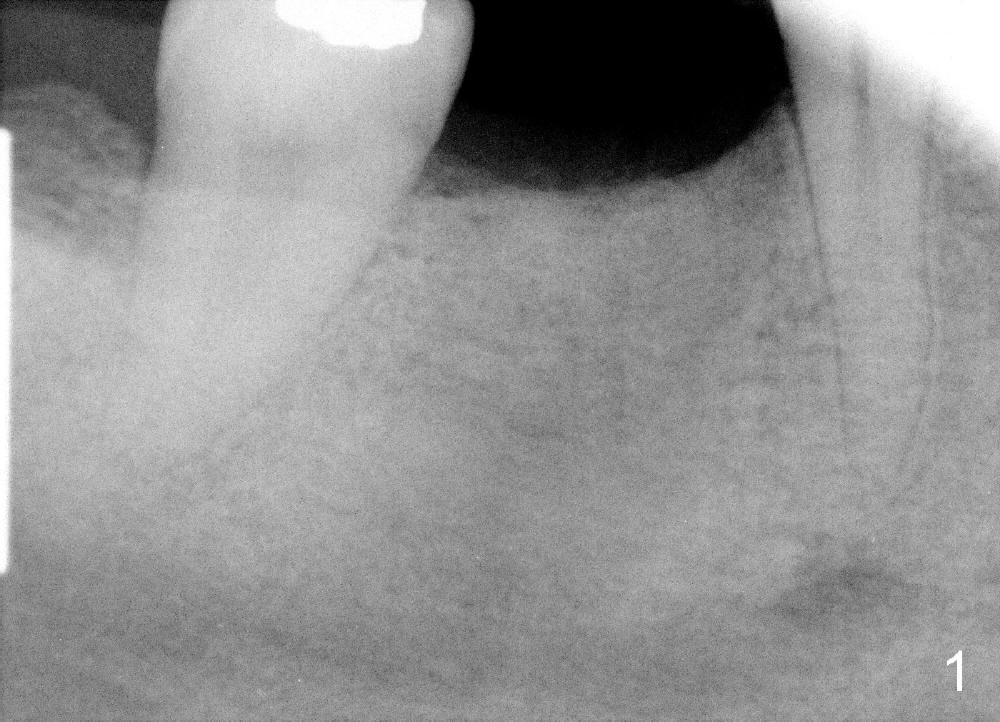

A 43-year-old lady presents to our office for implant 1 month post extraction. Treatment plan is to place a soft tissue level implant (1 stage). The surgery is finished as planned, but there is post-implant infection. The implant is removed with bone graft. Three months post implant removal, the socket heals (Fig.1) with wide ridge (Fig.2). Her oral hygiene remains not so pristine. To reduce the chance of infection, submerged implant is planned (2 stages). Oral Amoxicillin is taken preop.